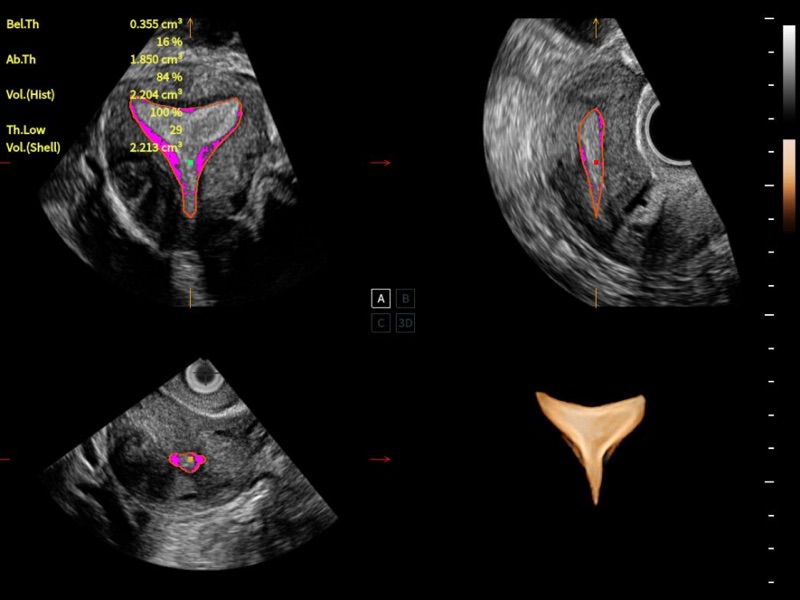

作为开立医疗全新打造的超高端旗舰超声产品,从探头抬起唤醒开启扫查到多维探头发射接收,通过先进的场成像发射、自适应聚合重建等技术,基于RF Data原始射频数据在图像生成、高端功能等方面实现突破,为妇产科、儿科提供全方位临床解决方案。

独有场成像发射技术

自适应聚合重建技术

独家XPUs混合硬件架构